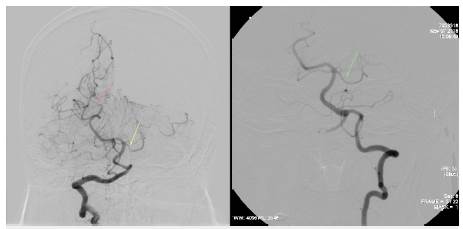

Mujer de 58 años de edad, ama de casa, ingresó por 15 días de evolución de cefalea de inicio hiperagudo pulsátil, en región occipital propagada a región frontal derecha, periorbitaria y nasal, intensidad 9/10, asociado a múltiples emesis, fosfenos y parestesias en manos. Había intensificación con la maniobra de Valsalva, no fue precedida de aura y no tuvo alteración de la conciencia u otro síntoma adicional. Los síntomas se presentaron durante una sesión de masaje en un spa, la paciente relató que en un momento le indicaron que realizara maniobras de Valsalva repetidamente y durante este periodo de tiempo se instaura la cefalea. Como antecedentes, tiene hipertensión arterial y dislipidemia en tratamiento con losartan 50 mg cada día y atorvastatina 40 mg cada noche, negaba abuso de alcohol o de tabaco, y una hija falleció por hemorragia subaracnoidea aneurismática 10 meses atrás. Se encontró deshidratada, con presión arterial 170/80 mmHg, frecuencia cardiaca 82/min; frecuencia respiratoria 20/ min; saturación de oxígeno 92% al ambiente. Talla 1,65 m, peso 78 kg, IMC 28 kg/m2, sin anormalidad en su exámen físico general. En el fondo de ojo se observaron arterias en hilo de cobre bilateral sin papiledema, no tuvo signos de irritación meníngea, no hubo alteración de otros pares craneanos ni de la fuerza o sensibilidad o coordinación. La resonancia cerebral simple mostró sangre en el espacio subaracnoideo de la cisura interhemisférica (Figura 1); dado esto y por el antecedente de la hija, se propuso practicar una panagiografía cerebral. Se trasladó a la unidad de cuidados intermedios y se inició terapia con nimodipino 60 mg cada 4 horas; no presentó deterioro neurológico y el seguimiento con doppler transcraneal no mostró signos de vasoespasmo. En la panangiografía cerebral no se identificaron aneurismas ni malformaciones arteriovenosas o fístulas, sin embargo, en arterias de mediano y pequeño calibre tanto en territorio anterior como posterior se evidenciaron múltiples estenosis y dilataciones segmentarias generando la imagen de "salchichas atadas" (Figuras 2 a 4). Se hizo la solicitud de perfil autoinmune para evaluar dentro del diagnóstico diferencial vasculitis sistémica, los resultados de los anticuerpos fueron: factor reumatoide negativo, C3 146 (normal), C4 28,7 (normal), anticuerpos antimieloperoxidasa negativos, anticuerpos antiproteinasa 3 negativos, anticuerpos antinucleares negativos.

Figura 4: Arteriografía de las vertebrales. A la izquierda el estudio del ingreso evidencia constricción segmentaria de la arteria cerebelosa superior izquierda y ramas de la cerebral posterior derecha. A la derecha el estudio control a los 3 meses demuestra su normalización.

Teniendo en cuenta la presentación clínica, los hallazgos angiográficos dados por la ausencia de signos de arrosariamiento vascular, la presencia de estrechez y dilatación vascular segmentaria, la carencia de manifestaciones sistémicas de enfermedad reumatológica, y la no exposición a medicamentos vasoactivos, inmunosupresores u otra etiología; se consideró con más certeza el síndrome de vasoconstricción cerebral reversible desencadenado por maniobras de Valsalva. Para el diagnóstico diferencial de la angiitis primaria del sistema nervioso central se realizó punción lumbar para descartar inflamación en el líquido cefalorraquídeo; la presión de apertura fue de 25 cmH2O, glucorraquia 57 mg/dl (glucemia 74,9 mg/dl), proteinorraquia 32 mg/dl, leucocitos 6 células/µl, VDRL no reactivo. Se observó a la paciente durante 14 días en la institución, en este periodo la cefalea resolvió y no hubo recurrencia, tampoco hubo síntomas o signos nuevos; los estudios de doppler transcraneal de seguimiento no mostraron vasoespasmo. A la salida estaba asintomática y sin secuelas neurológicas, completando 3 semanas de tratamiento con nimodipino. A los 3 meses el control angiográfico mostró normalización de la estrechez segmentaria vascular (Figuras 3 a 4).